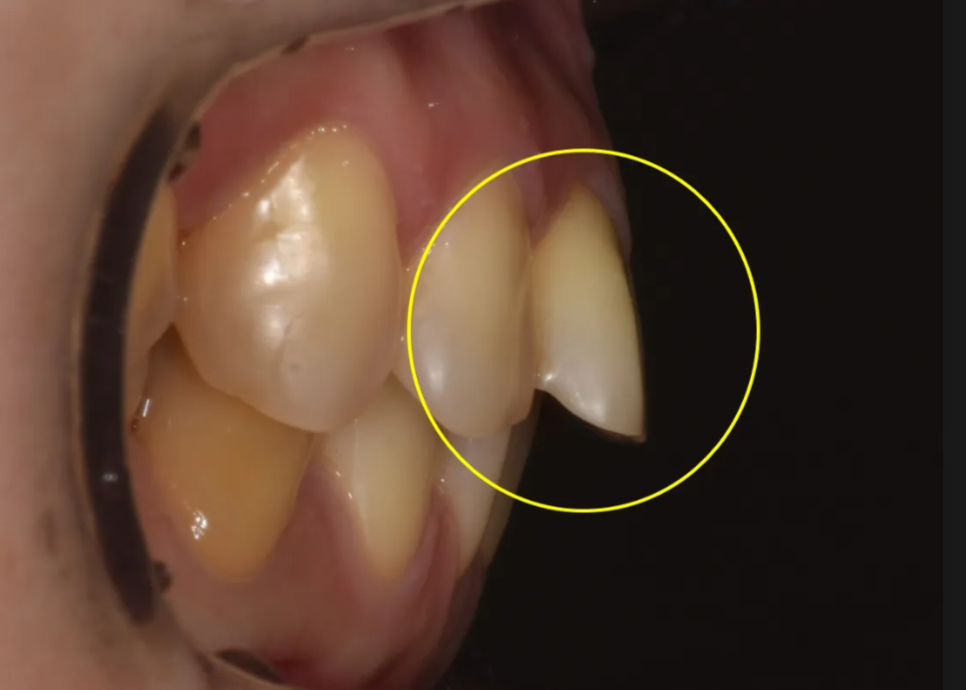

아랫니 앞니 부분의 문제점

오른쪽 앞니 부분 삐뚤어짐, 가운데 앞니 벌어짐

아랫니 쪽도 문제가 여럿 있었습니다. 오른쪽 앞니 두 개가 살짝 삐뚤어져 있었고, 가운데 아랫 앞니 사이에는 벌어진 공간이 있었습니다. 왼쪽 송곳니부터 두번째 작은어금니까지는 잇몸 경계 부위가 마모(치경부 마모)되어 있는 상태였습니다.

이 외에도 위아래 정중선(치아 가운데 라인)이 서로 일치하지 않았고, 위아래 앞니의 교합이 상당히 긴밀한 상태여서 이 역시 치료 시 고려가 필요했습니다.